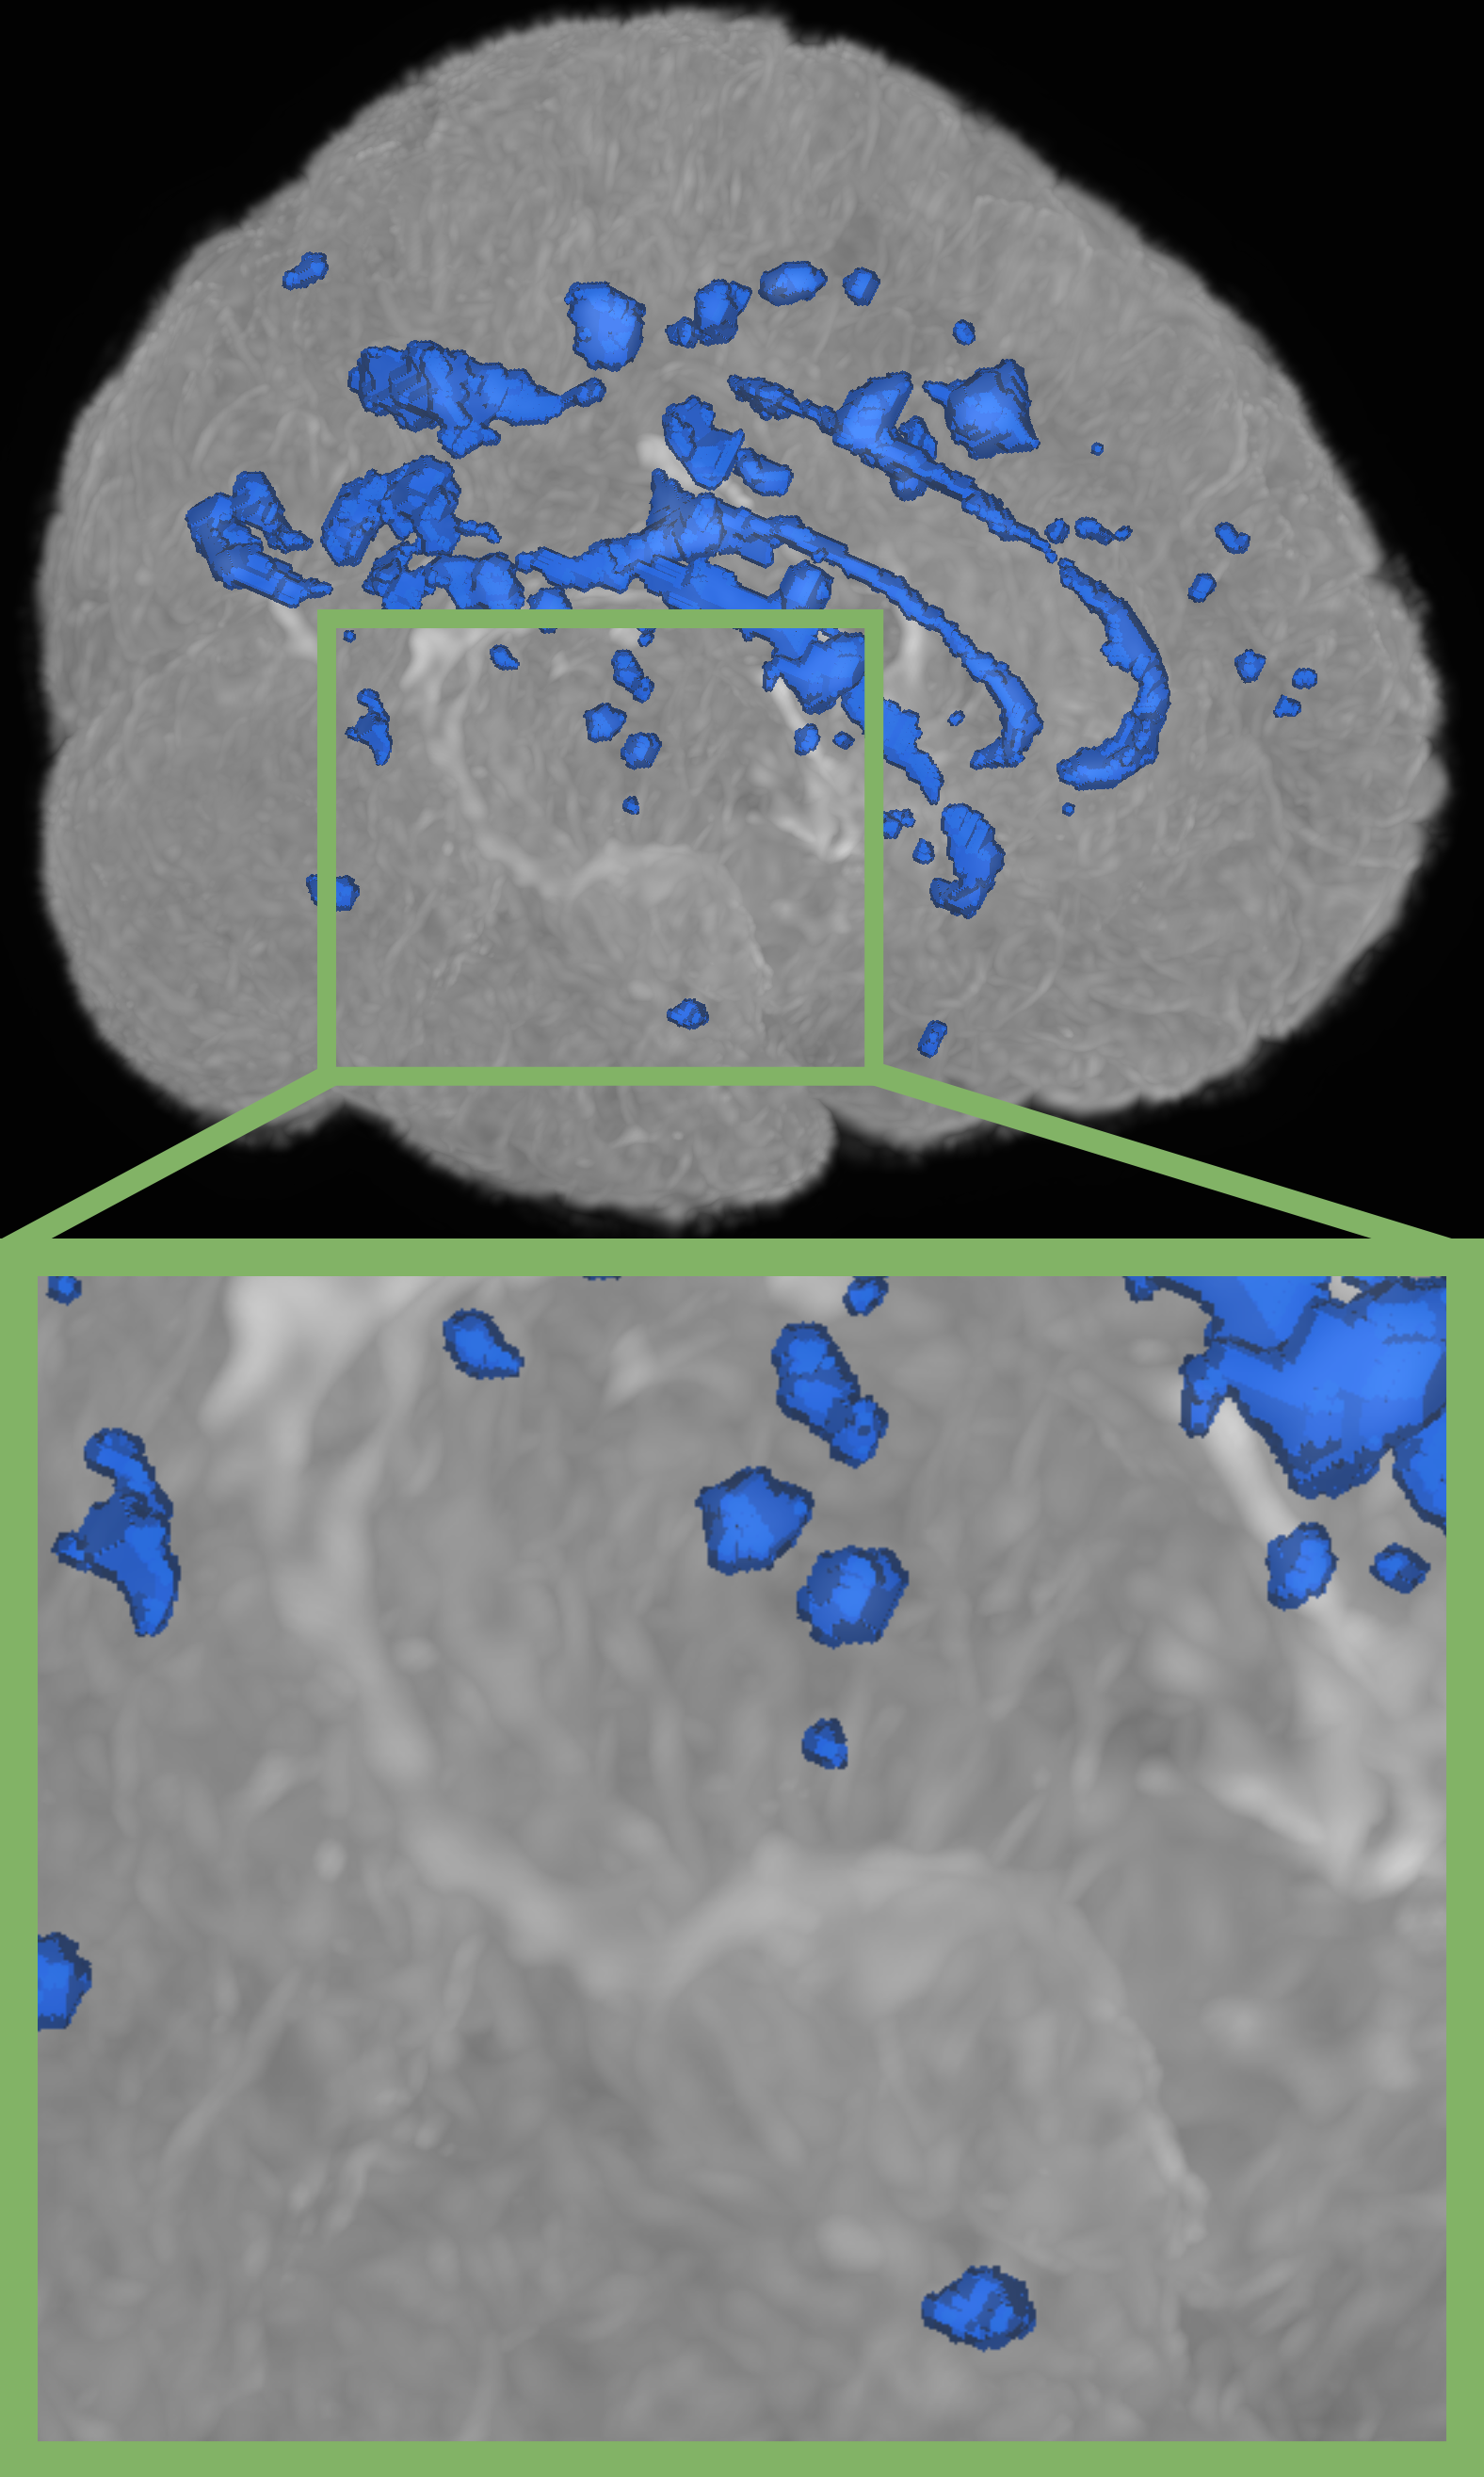

Refer to caption

(a) nnUNet[16]

(b) Szeskin et.al.[24]

(c) Difference Weighting (Ours)

(d) Ground Truth

Figure 2: Qualitative results on the Ljubljana dataset. Compared to related work, our proposed method demonstrates superior performance in volumetric delineation of MS lesions and successfully identifies lesions missed by other methods.

Table 2 illustrates SOTA performance against several established single and multi timepoint baselines on the Ljubljana dataset. We also show the generalizability of our best models on the ISBI 2015 dataset in Tab. 3 respectively. Figure 2 shows additional qualitative results on the Ljubljana dataset. Overall, we demonstrate the following findings:

Powerful single timepoint networks outperform existing longitudinal approaches: nnUNet[16], as the best single timepoint model, achieves a Dice score of 74.16%, a 95% Hausdorff Distance of 4.95mm and a lesion-based F1 score of 71.27% on the test set of the Ljubljana dataset. The results clearly show that current longitudinal approaches consistently struggle to surpass or even reach this performance. The most competitive longitudinal baseline, a reimplementation of Szeskin et.al.’s method [24] within the nnUNet framework, still performs worse than nnUNet on all metrics, especially falling short 2.19% in lesion-based F1 score. The other two deep learning based baselines from Denner et al.[10] and Wu el.al.[25] demonstrate even lower performances with large decreases in all metrics. The non deep learning based FreeSurfer Samseg tool[6] achieves the worst results with a Dice score of 45.54%, a 95% Hausdorff distance of 15.84mm and a lesion-based F1 score of 33.05%.

Pairing powerful single timepoint methods with longitudinal data enables efficient use of additional information: While nnUNet on single timepoints outperforms inefficient longitudinal methods, the ablation of naively integrating longitudinal data into nnUNet through color channel concatenation (Longitudinal nnUNet) delivers enhancements across all investigated metrics when compared to previous longitudinal methods and SOTA single timepoint approaches. This underlines the potential gain longitudinal data can have even just as an additional channel input of a powerful single timepoint network.